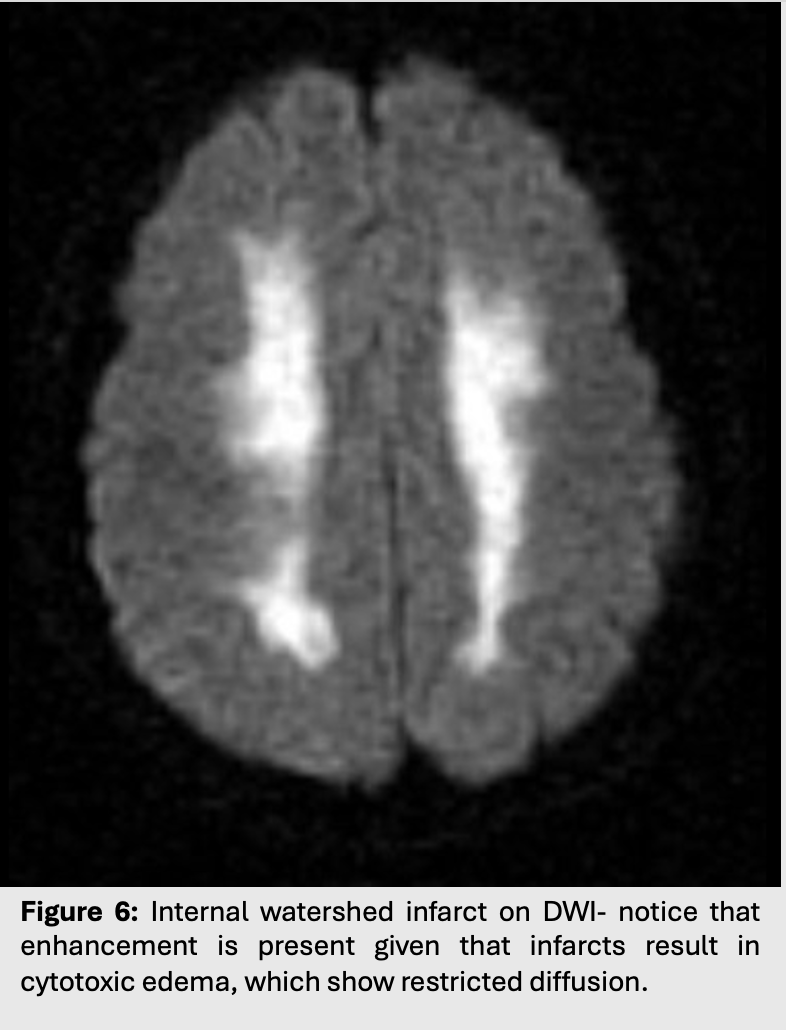

Figure 6: Internal watershed infarct on DWI- notice that enhancement is present given that infarcts result in cytotoxic edema, which show restricted diffusion.

• Infarcts of this kind are called watershed or border zone infarcts as they happen on the borders of major vascular territories.

• In these scenarios, the first areas of the brain to suffer from ischemia will be those furthest away from major arteries.